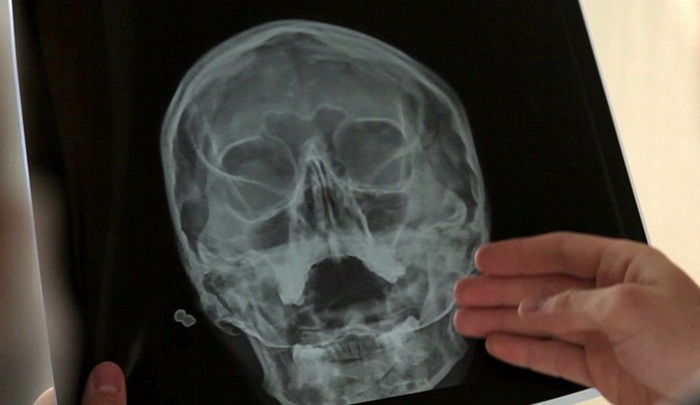

Обследование дает возможность доктору выявить переломы, кисты, опухоли, деформации. Метод позволяет быстро выявить наличие остеопороза. Также диагностика позволяет обнаруживать опухоли гипофиза, гематомы посттравматические, оценивать давление внутричерепное, выявляя в области височной гипер- и гипотензии.

Результатом обследования в проекции по Шуллеру является информативный снимок. По снимку врач может выявить доброкачественные опухоли и злокачественные новообразования в височной области. Также по снимку можно определить степень сложности переломов и ушибов височной области, детально изучить структуры костей и тканей в различных проекциях. Кроме того, снимок позволяет отслеживать ход лечения при заболеваниях уха.